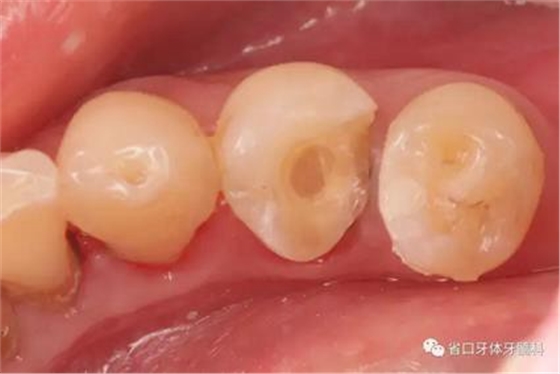

圖4:牙體預備術前照

圖5:顯微鏡下34牙體預備,拋光,35近中樹脂直接充填,選色偏白